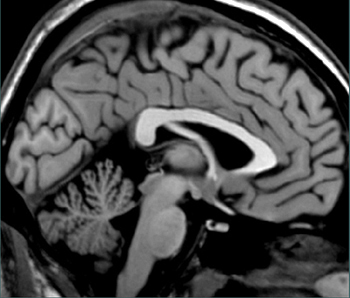

Locate (click on) the tentorium.